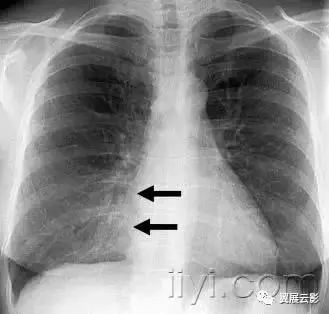

六十四、网状影

平片和CT.—在胸片上,网状影是大量细线状影的聚集,简言之,就是形成网状外观,(图)本征象一般代表间质性肺疾病。薄层CT显示网状影的成份更加清晰,可以是小叶间隔、小叶内线的增厚,或者是蜂窝征的囊壁。注意网状影和蜂窝征不是同义词。